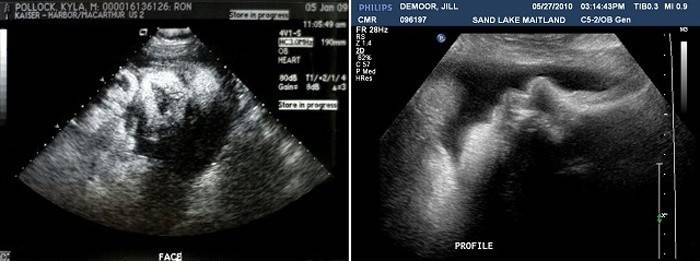

Badanie ultrasonograficzne (Uzi)

W tej chwili planowane USG nie jest już wykonywane, lekarz może przepisać ultradźwięki, aby rozwiązać pilne problemy podczas planowania cięcia cesarskiego lub rozwiązać problem porodu. Ultradźwięki są zwykle przepisywane we wcześniejszych badaniach z identyfikacją splątania pępowiny, a także w celu ustalenia ilości płynu owodniowego, stanu łożyska, jego dojrzałości i lokalizacji płodu w macicy, szyjce macicy. Przeprowadzana jest również ocena rozwoju płodu, jego szacowanego wzrostu masy i udoskonalenia DA zgodnie z danymi ultrasonograficznymi. Ważne jest, aby określić rozmiar głowy i klatki piersiowej płodu, długość dużych kości.

Również po 38 tygodniach, zgodnie z ultradźwiękami, określa się rozmiar szyjki macicy, jej dojrzałość i stan gotowości do porodu.